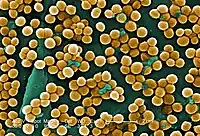

Linezolid is an antibiotic used for the treatment of infections caused by Gram-positive bacteria that are resistant to other antibiotics.[1][3] Linezolid is active against most Gram-positive bacteria that cause disease, including streptococci, vancomycin-resistant enterococci (VRE), and methicillin-resistant Staphylococcus aureus (MRSA).[3][4] The main uses are infections of the skin and pneumonia although it may be used for a variety of other infections including drug-resistant tuberculosis.[1][5] It is used either by injection into a vein or by mouth.[1]

Spectrum of activity

Linezolid is effective against all clinically important Gram-positive bacteria—those whose cell wall contains a thick layer of peptidoglycan and no outer membrane—notably Enterococcus faecium and Enterococcus faecalis (including vancomycin-resistant enterococci), Staphylococcus aureus (including methicillin-resistant Staphylococcus aureus, MRSA), Streptococcus agalactiae, Streptococcus pneumoniae, Streptococcus pyogenes, the viridans group streptococci, Listeria monocytogenes, and Corynebacterium species (the latter being among the most susceptible to linezolid, with minimum inhibitory concentrations routinely below 0.5 mg/L).[4][52][65] Linezolid is also highly active in vitro against several mycobacteria.[52] It appears to be very effective against Nocardia, but because of high cost and potentially serious adverse effects, authors have recommended that it be combined with other antibiotics or reserved for cases that have failed traditional treatment.[66]